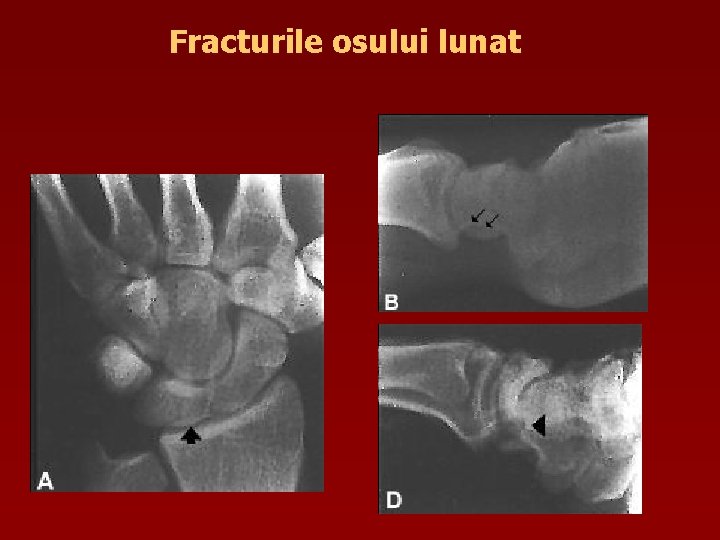

Fracturile osului lunat